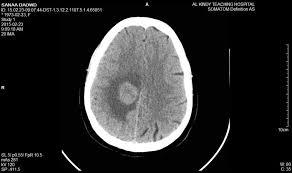

CT scan(cat scan) pros

3d X-RAY

Diagnostic of changes over time

Noninvasive and quick

CT scan(cat scan) clinical uses

See hemphorages( internal bleeding)

See tumor

See fractures and such

Damage to the meniges(increase contrast on picture)